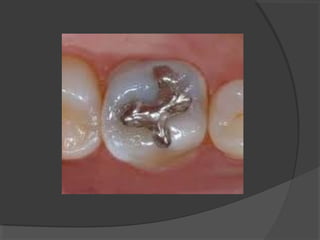

a) Class I Cavities:

Those cavities originating in anatomical pits and

fissures. They are found in the occlusal surface of

molars and premolars.